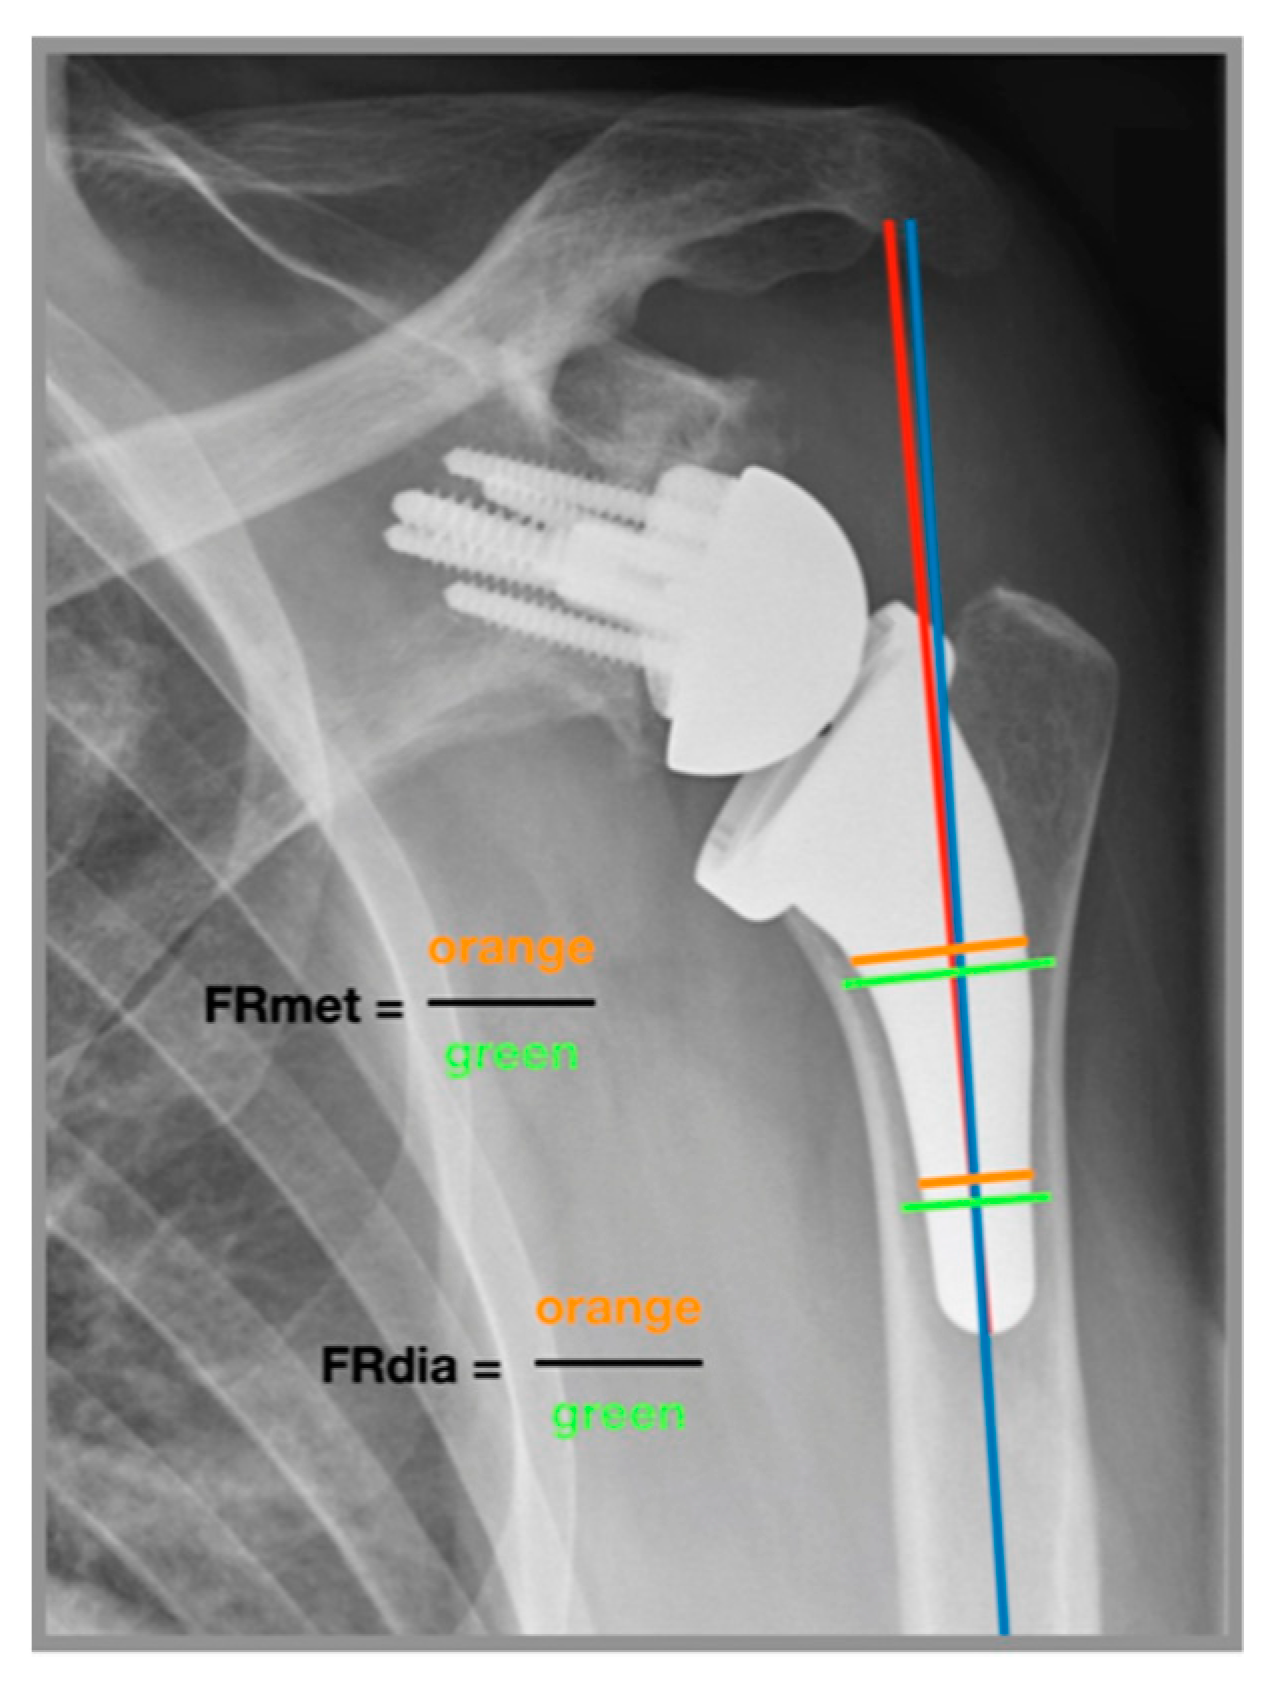

2.4. Radiographic Analysis

Two independent examiners performed radiographic measurements of 137 reverse USSPs on comparable anteroposterior radiographs immediately postoperatively and at final follow-up. Stem inclination (neutral/valgus/varus) was measured in degrees and the filling ratio of the humeral shaft was measured at the level of the metaphysis and diaphysis in millimeters according to the method introduced by Schnetzke et al. (Figure 2) [27]. If the angle of the stem relative to the humeral canal was ± 5 degrees, the inclination was considered as neutral. If the angle was >5 degrees the inclination was considered as valgus and if the angle was <5 degrees the inclination was considered as varus [31]. Cortical thickness was measured according to the method of Mather et al. [32]. Subsidence was determined by comparing the distance between the most cephalic aspect of the greater tuberosity with the distal border of the stem according to the method introduced by Bogle et al. (Figure 3) [33] and was empirically defined as an inferior migration of the shaft greater than 5 mm. Radiological results of patients who developed a postoperative complication were reported separately.

Figure 2. Measurement of filling ratio and alpha angle [27]. Anteroposterior radiograph of a left shoulder. The alpha angle (α) was measured between the shaft axis (blue line) and the stem axis (red line). Filling ration at the level of the metaphysis (FRmet) is a line perpendicular to the shaft axis, intersecting at the distal–medial border of the humeral platform. Filling ratio at the level of the diaphysis (FRdia) is a line perpendicular to the shaft axis, intersecting at the distal third of the prosthesis. The filling ratio is the quotient of the orange and green lines at the metaphysis (FRmet) and at the diaphysis (FRdia). Distances were calibrated based on the size of the glenosphere.